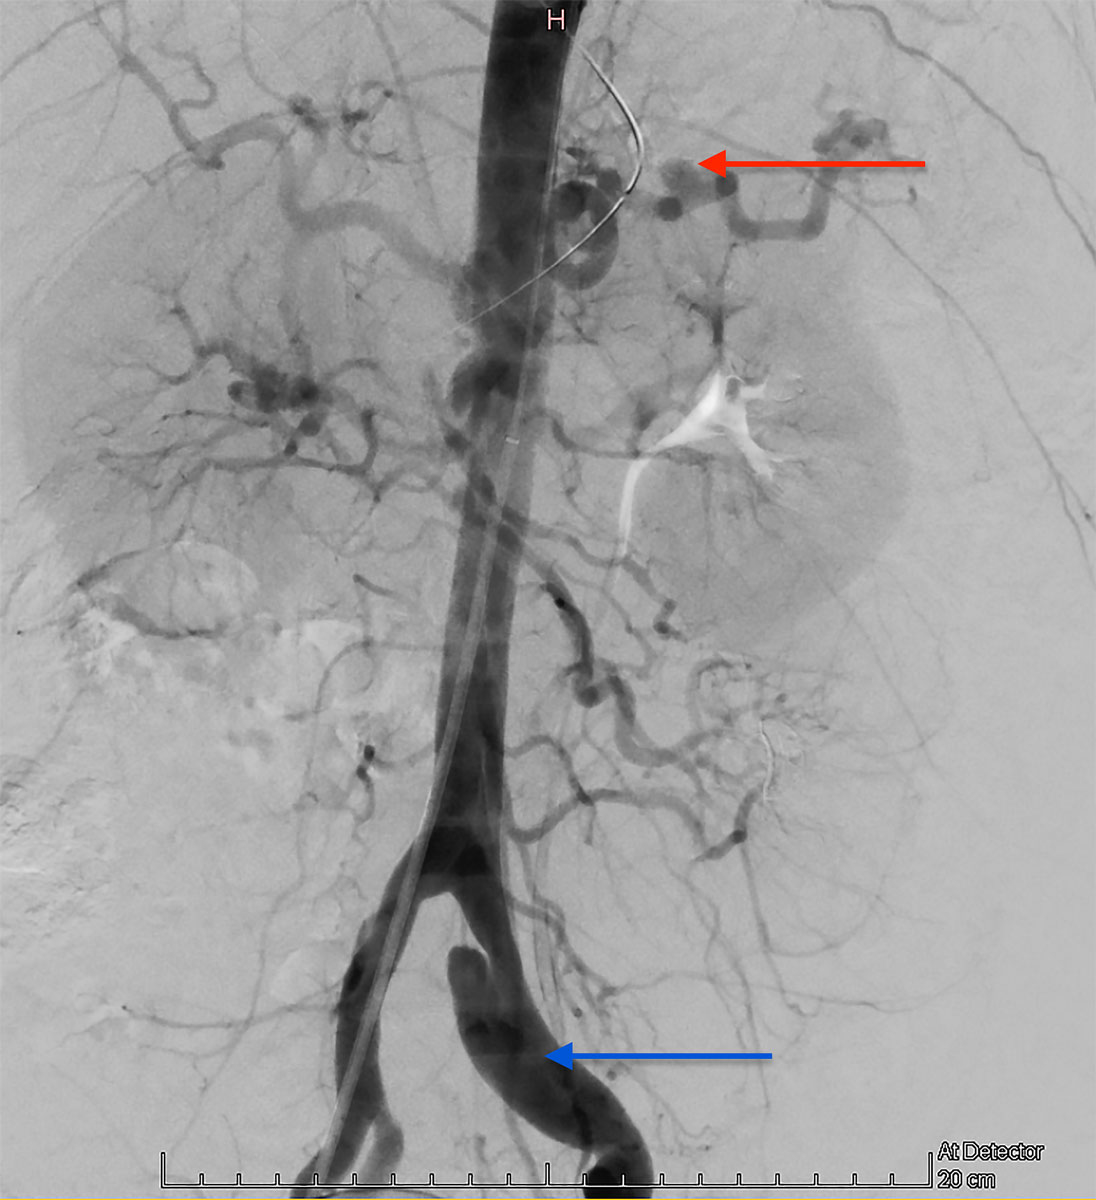

Selective embolisation was attempted as first-line therapy. Nevertheless, angiography failed to detect active haemorrhage in the territory of the inferior mesenteric artery. A balloon angioplasty of the superior mesenteric artery dissection was possible, however. This angiography confirmed the pathological aspect of the splanchnic arteries, suggesting a systemic vascular condition (fig. 4).

Figure 4 Emergency angiography showing a pathological aspect of the splanchnic arteries, suggesting a systemic vascular condition (splenic artery aneurysm – red arrow – and left common iliac artery dissection – blue arrow). No active haemorrhage in the territory of the inferior mesenteric artery was found.